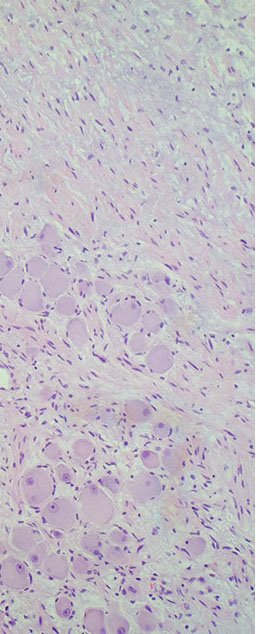

Subependymal Giant Cell Astrocytoma (SEGA!!!)

Assoc c tuberous sclerosis (>9/10); WHO grade I

Found in medial wall of lat ventricles, may block formen of Monroe, causing hydrocephalus

- also has strong assoc c epilepsy (remove to stop seizures)

- develop in first 2 decades of pts c tuberous sclerosis

- not just an astrocytome, also has neural and glial cells

Micro: pleomorphic prolif of bizarre "confused cells" - mixed neuronal and gangliocytic differentiation

- although the cytoplasm appears astrocytic (homogenous, eosinophilic), the nuclei often have neuronal features (granular chromatin, prominent nucleoli)

- "confused cells" can also be seen in cortical dysplasia

Although may see lots of nuclear pleomorphism, there are no mits and Ki67 is low (looks bad, but has a good prognosis)

- tumor often has dystrophic calcifications

Cave canum: this tumor is rare and may be overcalled as a glioblastoma

DDx: subependymoma, central neurocytoma, choroid plexus papilloma, pleomorphic xanthoastrocytoma

IHC: Block (+) for S-100, (+) GFAP (glial component), and NFP (in neural component)